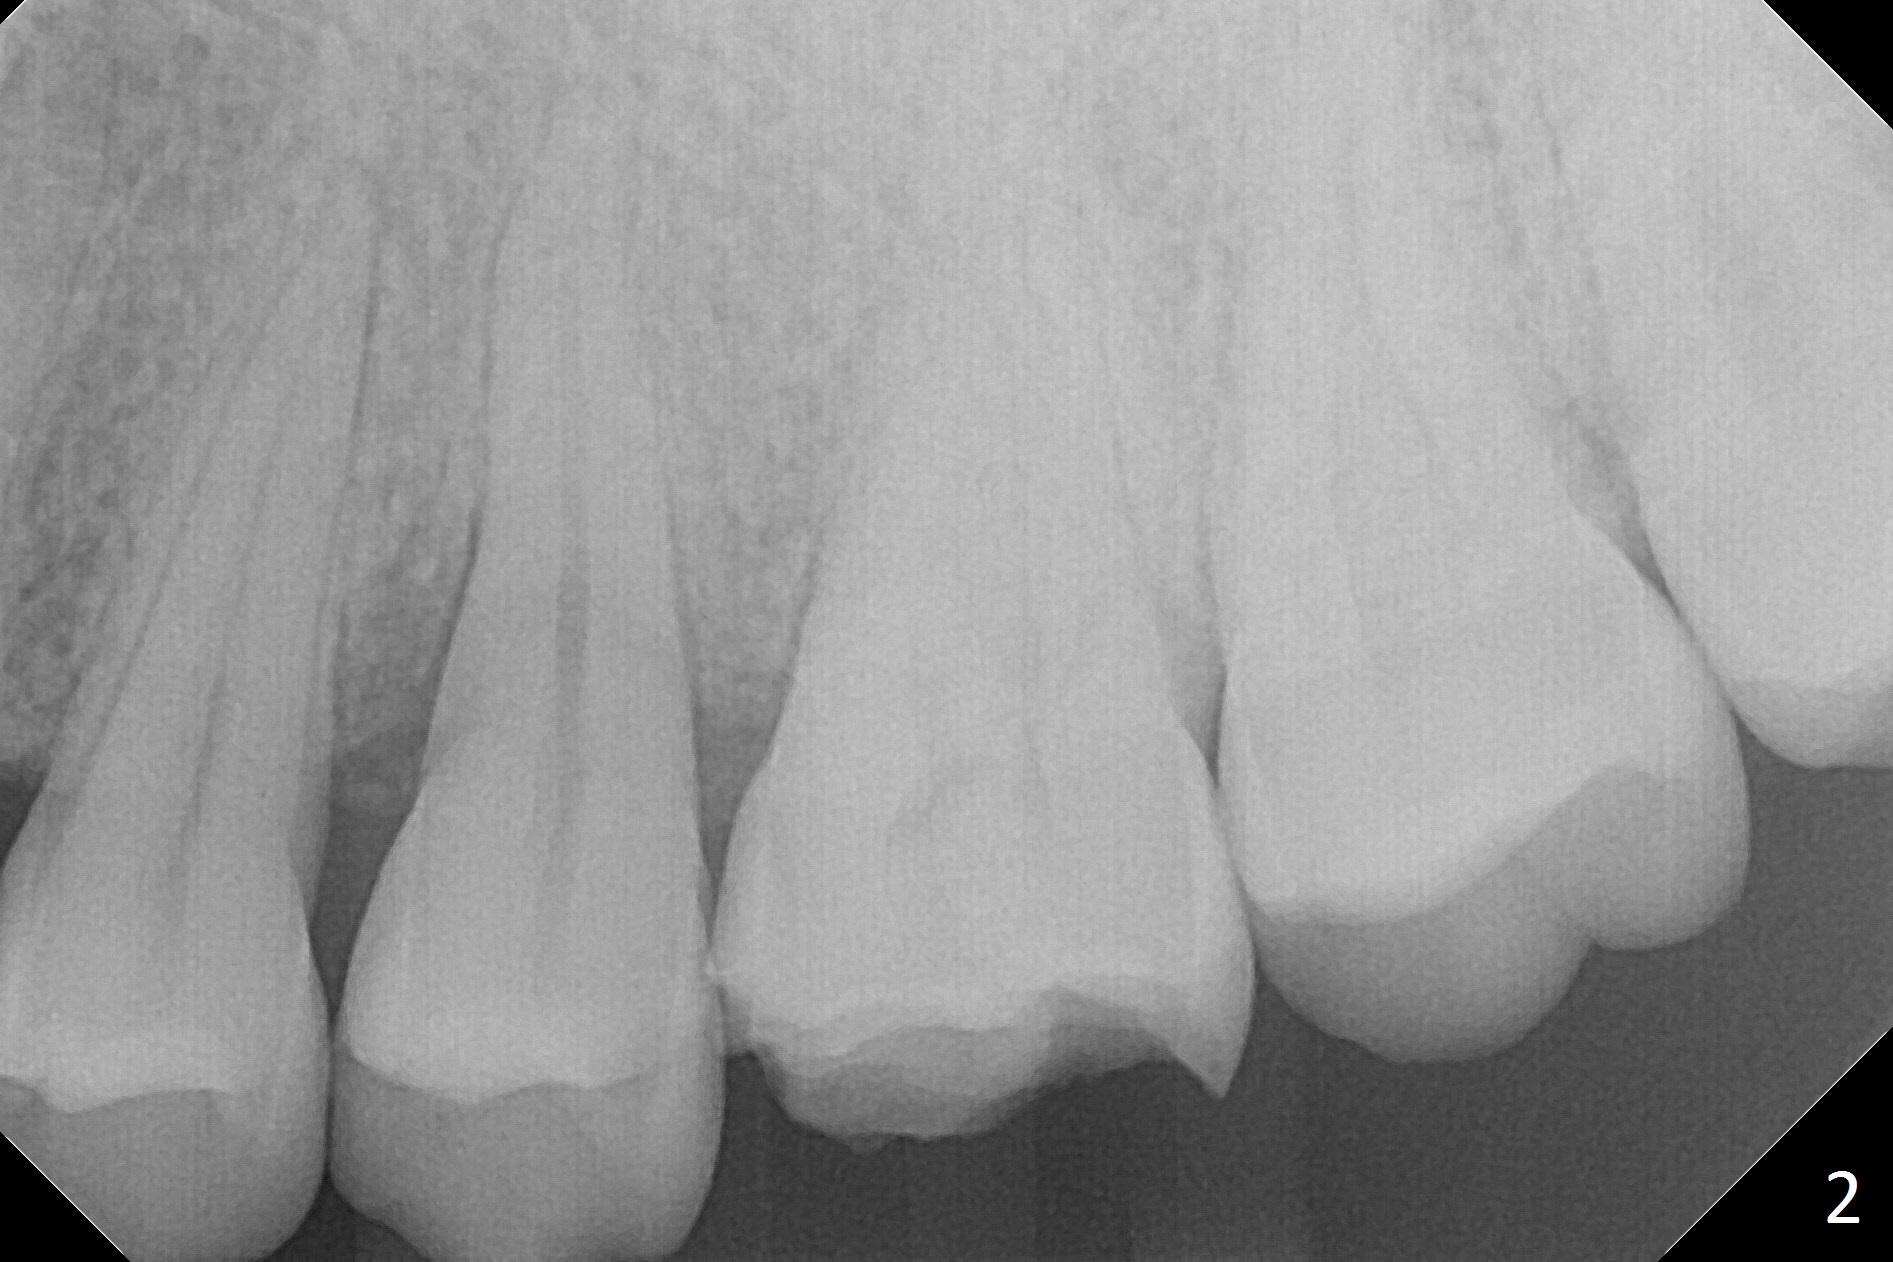

A 42-year-old woman presents to clinic with cc "top left tooth cracks upon biting on a small piece of stone". The buccal gingiva is tender, corresponding to the loose buccal segment of the tooth #13 (Fig.1). The crack may be secondary to severe wear of the 1st molar (Fig.1,2) in addition to deep slope of the affected tooth. A 4.5x15 mm IBS implant will be placed (Fig.3). Take PA following pilot drilling.